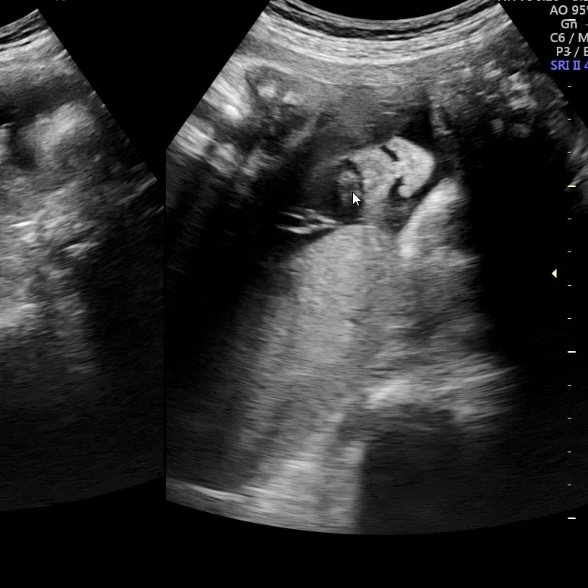

심박수는 150bpm.

동글동글한 튼튼한 눈코입?

어쩐지 짓궂게 생겼다.wwwwwwwww

몸무게는 곧 2kg이다.

“우리 집 건장이 참 많이 컸구나?전체적으로 골고루 자란 건장이야!”

엄마는 건장한 사람이 머리만 너무 크지마?